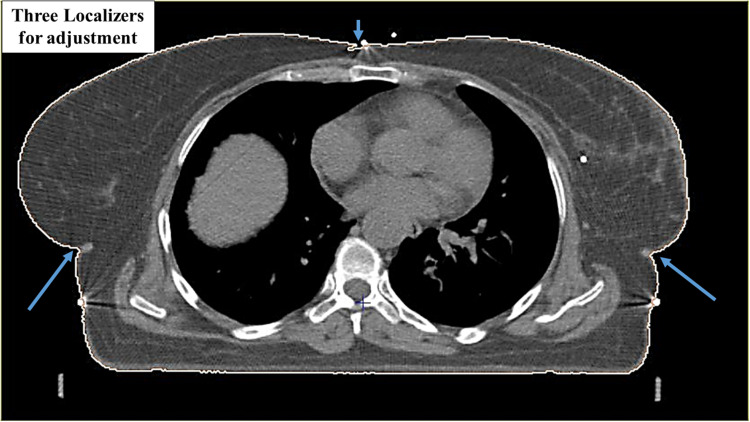

Patients and methods: A total of 15 patients diagnosed with left breast cancer with disease involved lymph nodes were included in this study. Delivering the recommended dose required the use of a linear accelerator (LINAC) with photon beams energy of 6 mega voltage (6MV). Each patient had full breast radiation using two planning procedures: intensity-modulated radiotherapy (IMRT) and three-dimensional radiotherapy (3D conformal). Following the guidelines set forth by the Radiation Therapy Oncology Group (RTOG), the planned treatment coverage was carefully designed to fall between 95% and 107% of the recommended dose. Additionally, Dose Volume Histograms (DVHs) were generated the dose distribution within these anatomical contours.

Results and conclusion: The DVH parameters were subjected to a comparative analysis, focusing on the doses absorbed by both Organs at Risk (OARs) and the Planning Target Volume (PTV). The findings suggest that low doses in IMRT plan might raise the risk of adverse oncological outcomes or potentially result in an increased incidence of subsequent malignancies. Consequently, the adoption of inverse IMRT remains limited, and the decision to opt for this therapy should be reserved for situations where it is genuinely necessary to uphold a satisfactory quality of life. Additionally, this approach helps in reducing the likelihood of developing thyroid problems and mitigates the risk of injuries to the supraclavicular area and the proximal head of the humerus bone.